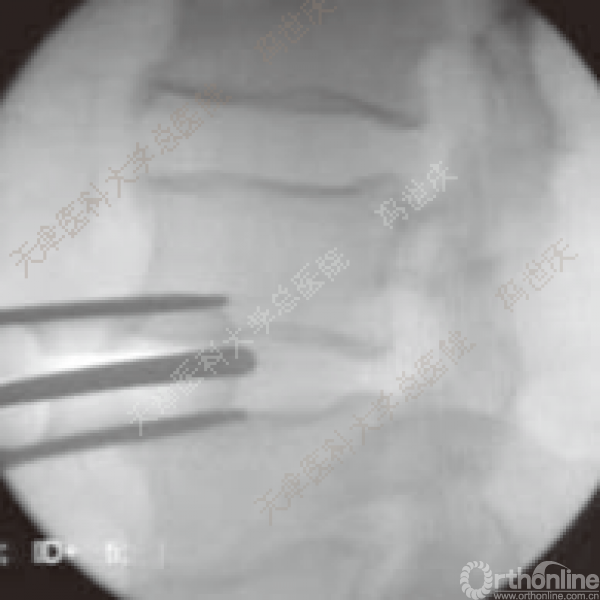

刨刀位于正中

刨刀清扫终板